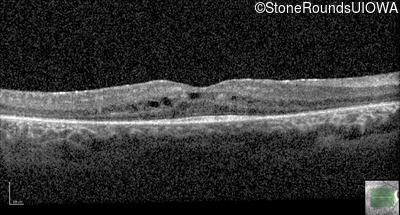

Optical Coherence Tomography - Left - 20/32

Exemplar / OCT Stack